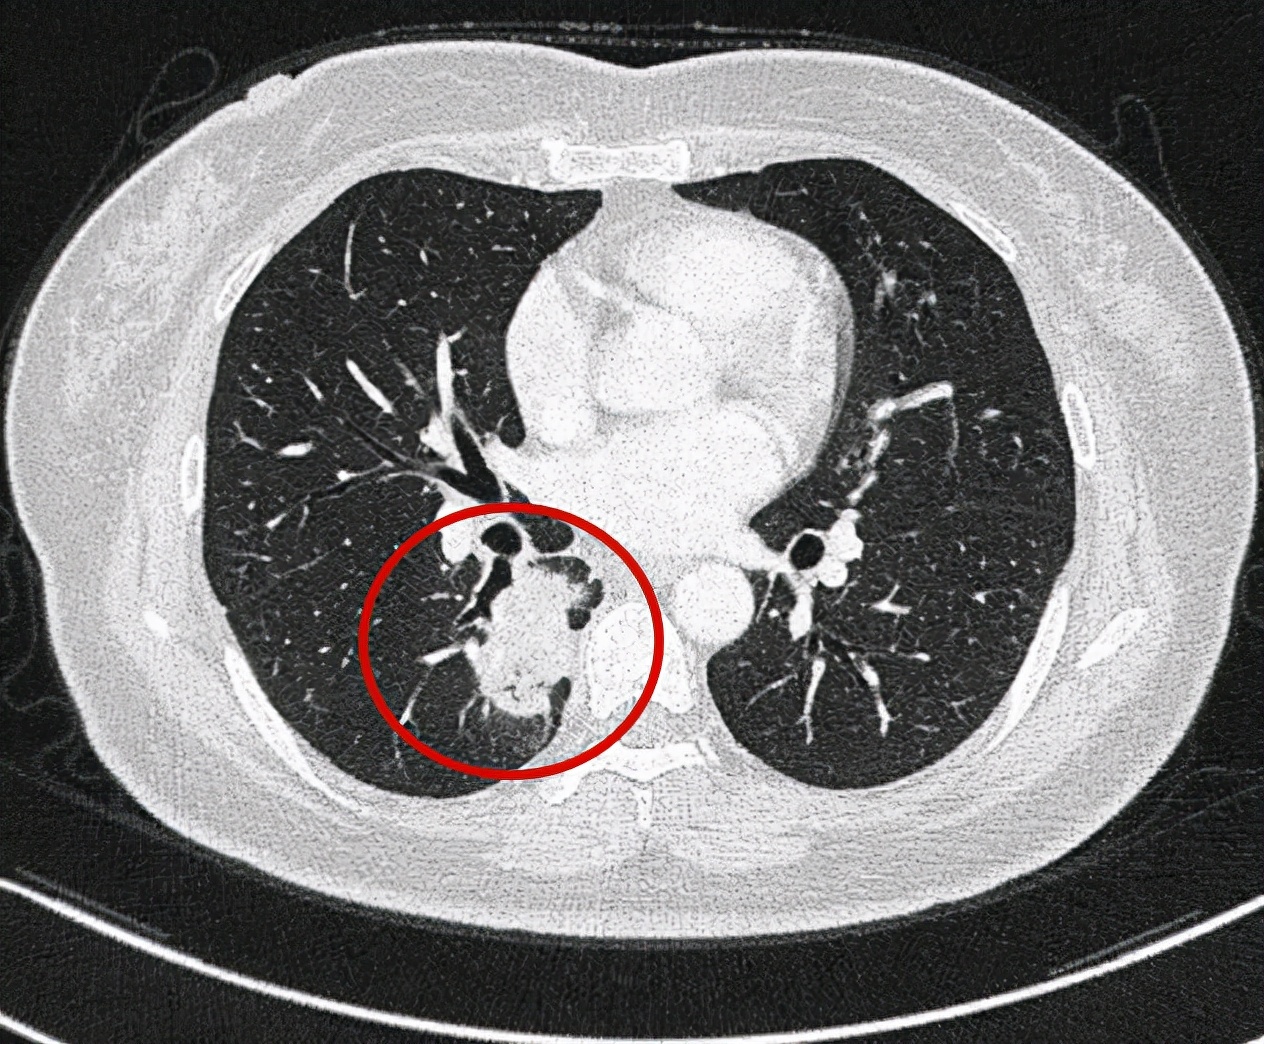

右下叶占位,有分叶、胸膜牵拉以边缘不规则等恶性征象

问诊建议:右下叶红色圈起来的考虑是肺癌,浸润性腺癌可能性大;右上叶磨玻璃结节粉色圈起来的考虑原位癌或不典型增生可能性大,不能完全除外微浸润性腺癌;绿色圈起来的基本上是叶裂处,从密度来看更像良性,但因为有右下叶的病灶在,且在叶间部位,也可能是种植转移,但术前较难确定。PET-CT可以考虑,但也有假阴性或假阳性。我的想法是如果没有远处其他确切转移,建议胸腔镜下探查,如果微小实性结节非转移性,则右下肺癌仍能手术的。如果真若是转移,也可取行病理依据,并送基因检测与免疫组化等检查,而单孔胸腔镜下探查下创伤小,恢复快,当然若不是转移,顺便镜下行右下叶切除并清扫淋巴结就行。